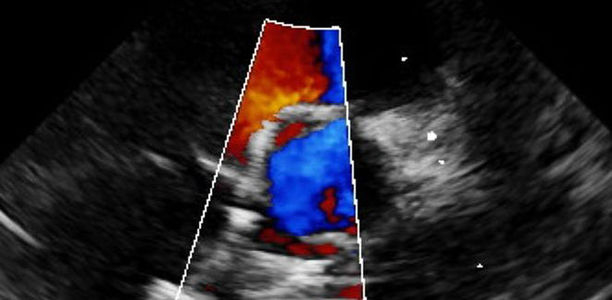

Angeborene Herzfehler werden zunehmend interventionell therapiert. Welche Interventionen sind möglich? Neben Dilatationen und dem Einbringen von Stents ist u.a. dere Pulmonalklappenbehandlung relativ häufig.

Interventionen bei angeborenen Herzfehlern